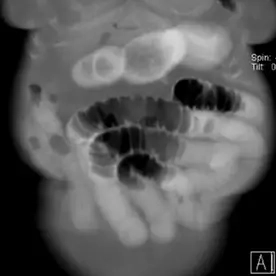

Die abdominale CT bestätigt den bereits klinisch geäußerten Verdacht auf einen Gallensteinileus. Es besteht ein mechanischer Dünndarmileus durch den obstruierenden großen Gallenstein prävalvulär an der Bauhin'schen Klappe sowie eine Aerobilie. Die Aerobilie kann sowohl durch die bereits durchgeführte ERCP mit Stentanlage als auch durch die Gallensteinpermeation bedingt sein.

Das Erscheinungsbild entspricht der Rigler-Trias und ist besser zu erkennen als im Röntgenbild. Da nur eine Minderheit der Gallensteine verkalken (12,5 %) und ihre Dichte dem normalen Darminhalt ähnelt, kann man den Gallenstein leicht übersehen. Kurz vor dem Übergang kann es zu einer Ausstülpung des Darms kommen, was bei der Lokalisierung des Gallensteins hilfreich sein kann. In der Regel sind die Steine groß und messen mehrere Zentimeter (2-3 cm).